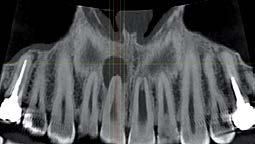

Nell’ambito della radiologia 3D ortopedica, il centro diagnostico utilizza il nuovissimo macchinario NewTom 5G XL, in grado di individuare con la massima precisione la presenza di fratture o lussazioni delle articolazioni, controllare la corretta guarigione di una frattura, valutare una lesione o una ferita causata da infezione, artrite o crescita anormale dell’osso.

Il tutto mediante una semplice e veloce scansione, grazie alla quale si otterranno diverse immagini in 3D ad altissima risoluzione e, per ottenere immagini ancora più nitide mediante un bassissimo dosaggio di radiazioni, gli esperti si avvalgono dell’innovazione racchiusa nella tecnologia Cone Beam.

Se con la radiologia tradizionale era necessario eseguire scansioni multiple, la novità introdotta dal macchinario NewTom 5G XL risiede nella capacità di fornire immagini ad alta risoluzione in un’unica scansione, mostrando nitidamente i dettagli delle articolazioni degli arti superiori e inferiori. Inoltre, a differenza della tecnologia 2D, la radiologia 3D ortopedica permette di individuare immediatamente alcune patologie come quella del metatarso, la quale richiede un allineamento visivo dedicato o una diagnosi delle micro fratture ossee.